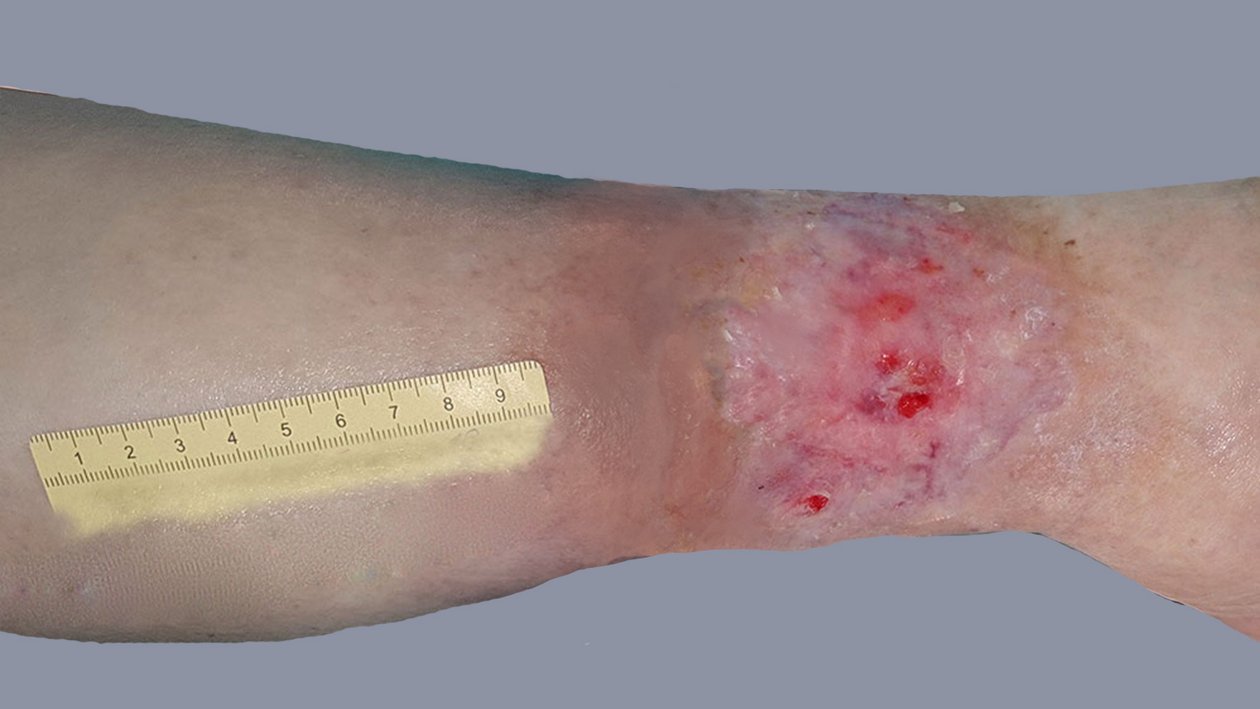

Stark exsudierende Wunde Tag 1

Foto 1: Stauungsproblematik und Keimbesiedelung (Tag 1)

Initial steht die Stauungsproblematik und die Keimbesiedelung im Mittelpunkt der Wundversorgung. Daher wird die Wundversorgung zunächst mit manueller Lymphdrainage und Anlage von Kurzzugkompressionsverbänden kombiniert. Die Wundabdeckung erfolgt zunächst mit einer PHMB-beschichteten Gaze und einem Superabsorber. Daneben wird die Patientin angeleitet, Bewegungsübungen und Übungen für eine verbesserte Funktion der Muskel-Venen-Pumpe durchzuführen. Damit diese Maßnahmen überhaupt möglich werden, wird sie einer angepassten Schmerztherapie zugeführt.